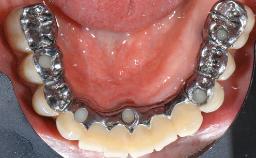

A 73-year-old woman was referred to the Division of Periodontology (University of Geneva School of Dental Medicine) after repeated unsuccessful treatment of a peri-implant infection. She was systemically healthy and did not smoke. The patient’s history revealed that, three years earlier, an immediate implant (Straumann Tapered Effect RN 4.8/4.1; Institut Straumann AG, Basel, Switzerland) had been inserted to replace the upper right central incisor. A metal-ceramic crown had been delivered using an adhesive resin cement. One year later, the patient had consulted another dentist due to discomfort in the soft tissues in the implant region. There was a suppurating peri-implant pocket, 10 mm deep. Peri-implant bone loss and excess luting cement were seen on the radiograph. The situation was treated with non-surgical debridement, amoxicillin, and repeated submucosal irrigation with a chlorhexidine digluconate solution. The patient was referred after the suppuration had persisted for several months.

Retention Cemented, with prosthesis margin > 3mm submucosal Cemented, with prosthesis margin > 3mm submucosal